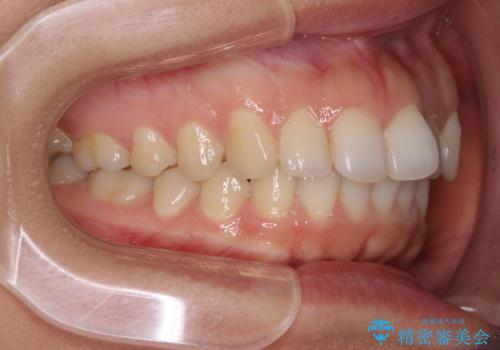

インビザライン矯正で前歯のデコボコを改善

- 前歯のデコボコを気にして来院された患者様です。

目立たないことを最優先にしたいとのことで、デコボコは軽度であったことから、インビザラインにて矯正治療を行うこととしました。

骨格的に下顎骨が左にずれており、上下の正中一致は困難ではありましたが、IPR(歯と歯の間を削る)や後方への移動など組み合わせて、できる限り改善しました。

インビザラインはマウスピースを外している時間が長いと、長期間使用しても前歯のデコボコはあまり改善されません。こちらの患者様は治療期間が長くなり、装着時間が短くなってしまったことで、気になる部分の改善により長期間を要するようになってしまいました。